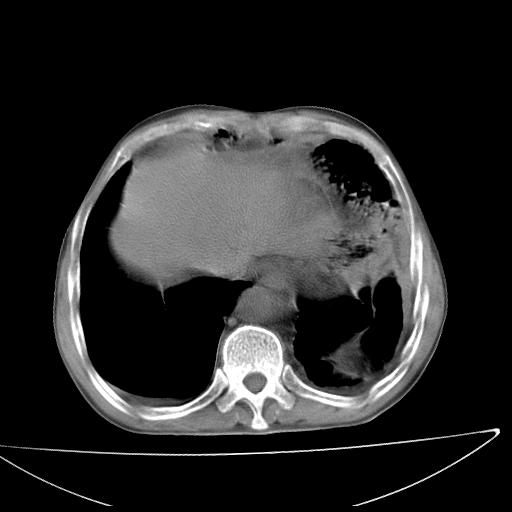

男  70岁,发烧咳嗽4天。盗汗,消瘦。无痰中带血丝,以前有肺tb病史,ct见,双肺tb,左侧胸廓塌陷,左胸膜肥厚粘连。纵隔移位,右侧胸腔积液,大家说说那个心影前左肺舌叶除了肺大炮还有炎症还是干酪性肺炎?有占位吗?我看纵隔淋巴结也大。

是胃,纵膈未见明显肿大淋巴结。

1)两肺继发性肺结核并左肺上叶肺不张,支气管扩张。2)双侧胸膜炎(胸膜增厚+少量胸腔积液)。

两肺继发性肺结核并感染,左肺上叶肺不张。建议ct增强。